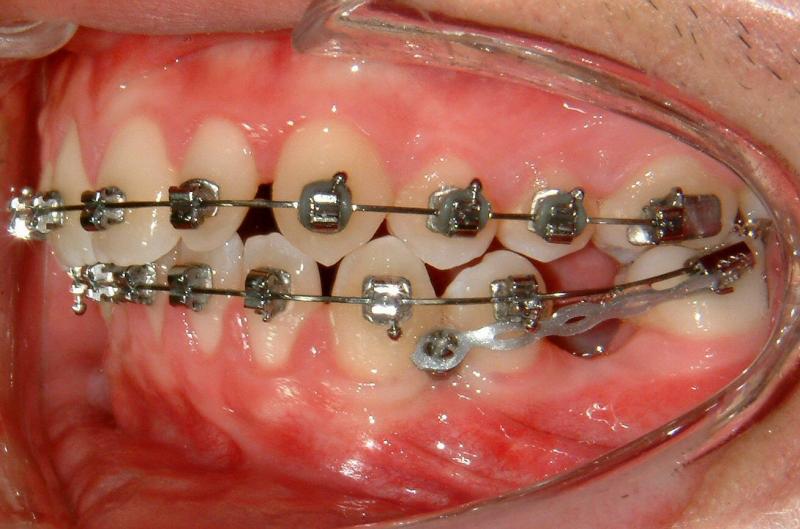

Fig. 7. Loading with NiTi spring (more effective)

© Copyright 2007-2014, Vu Orthodontics. All rights reserved.

The TAD is used as an absolute anchorage to protract LL6 without side effect. (The lower left canine will be moved forward later to achieve Class I canines.) An alternative mechanics may be used with a power arm to achieve a slightly more horizontal force but a bit complicated and less comfort (for the patient).